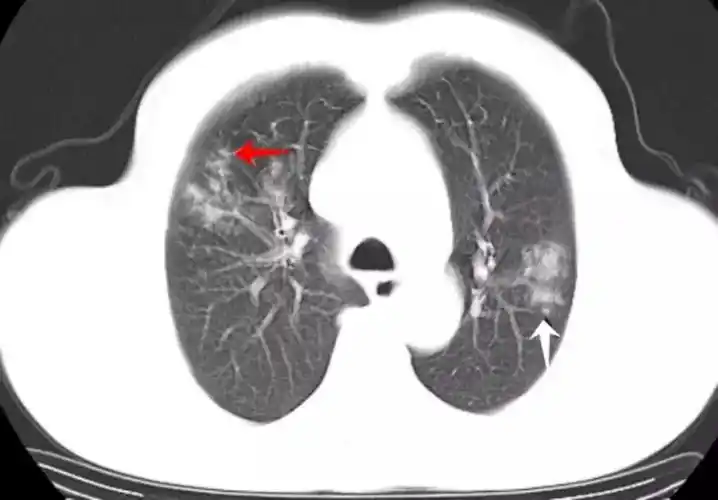

新型冠状病毒感染的肺炎ct影像学表现

【影像读片】病毒性肺炎ct